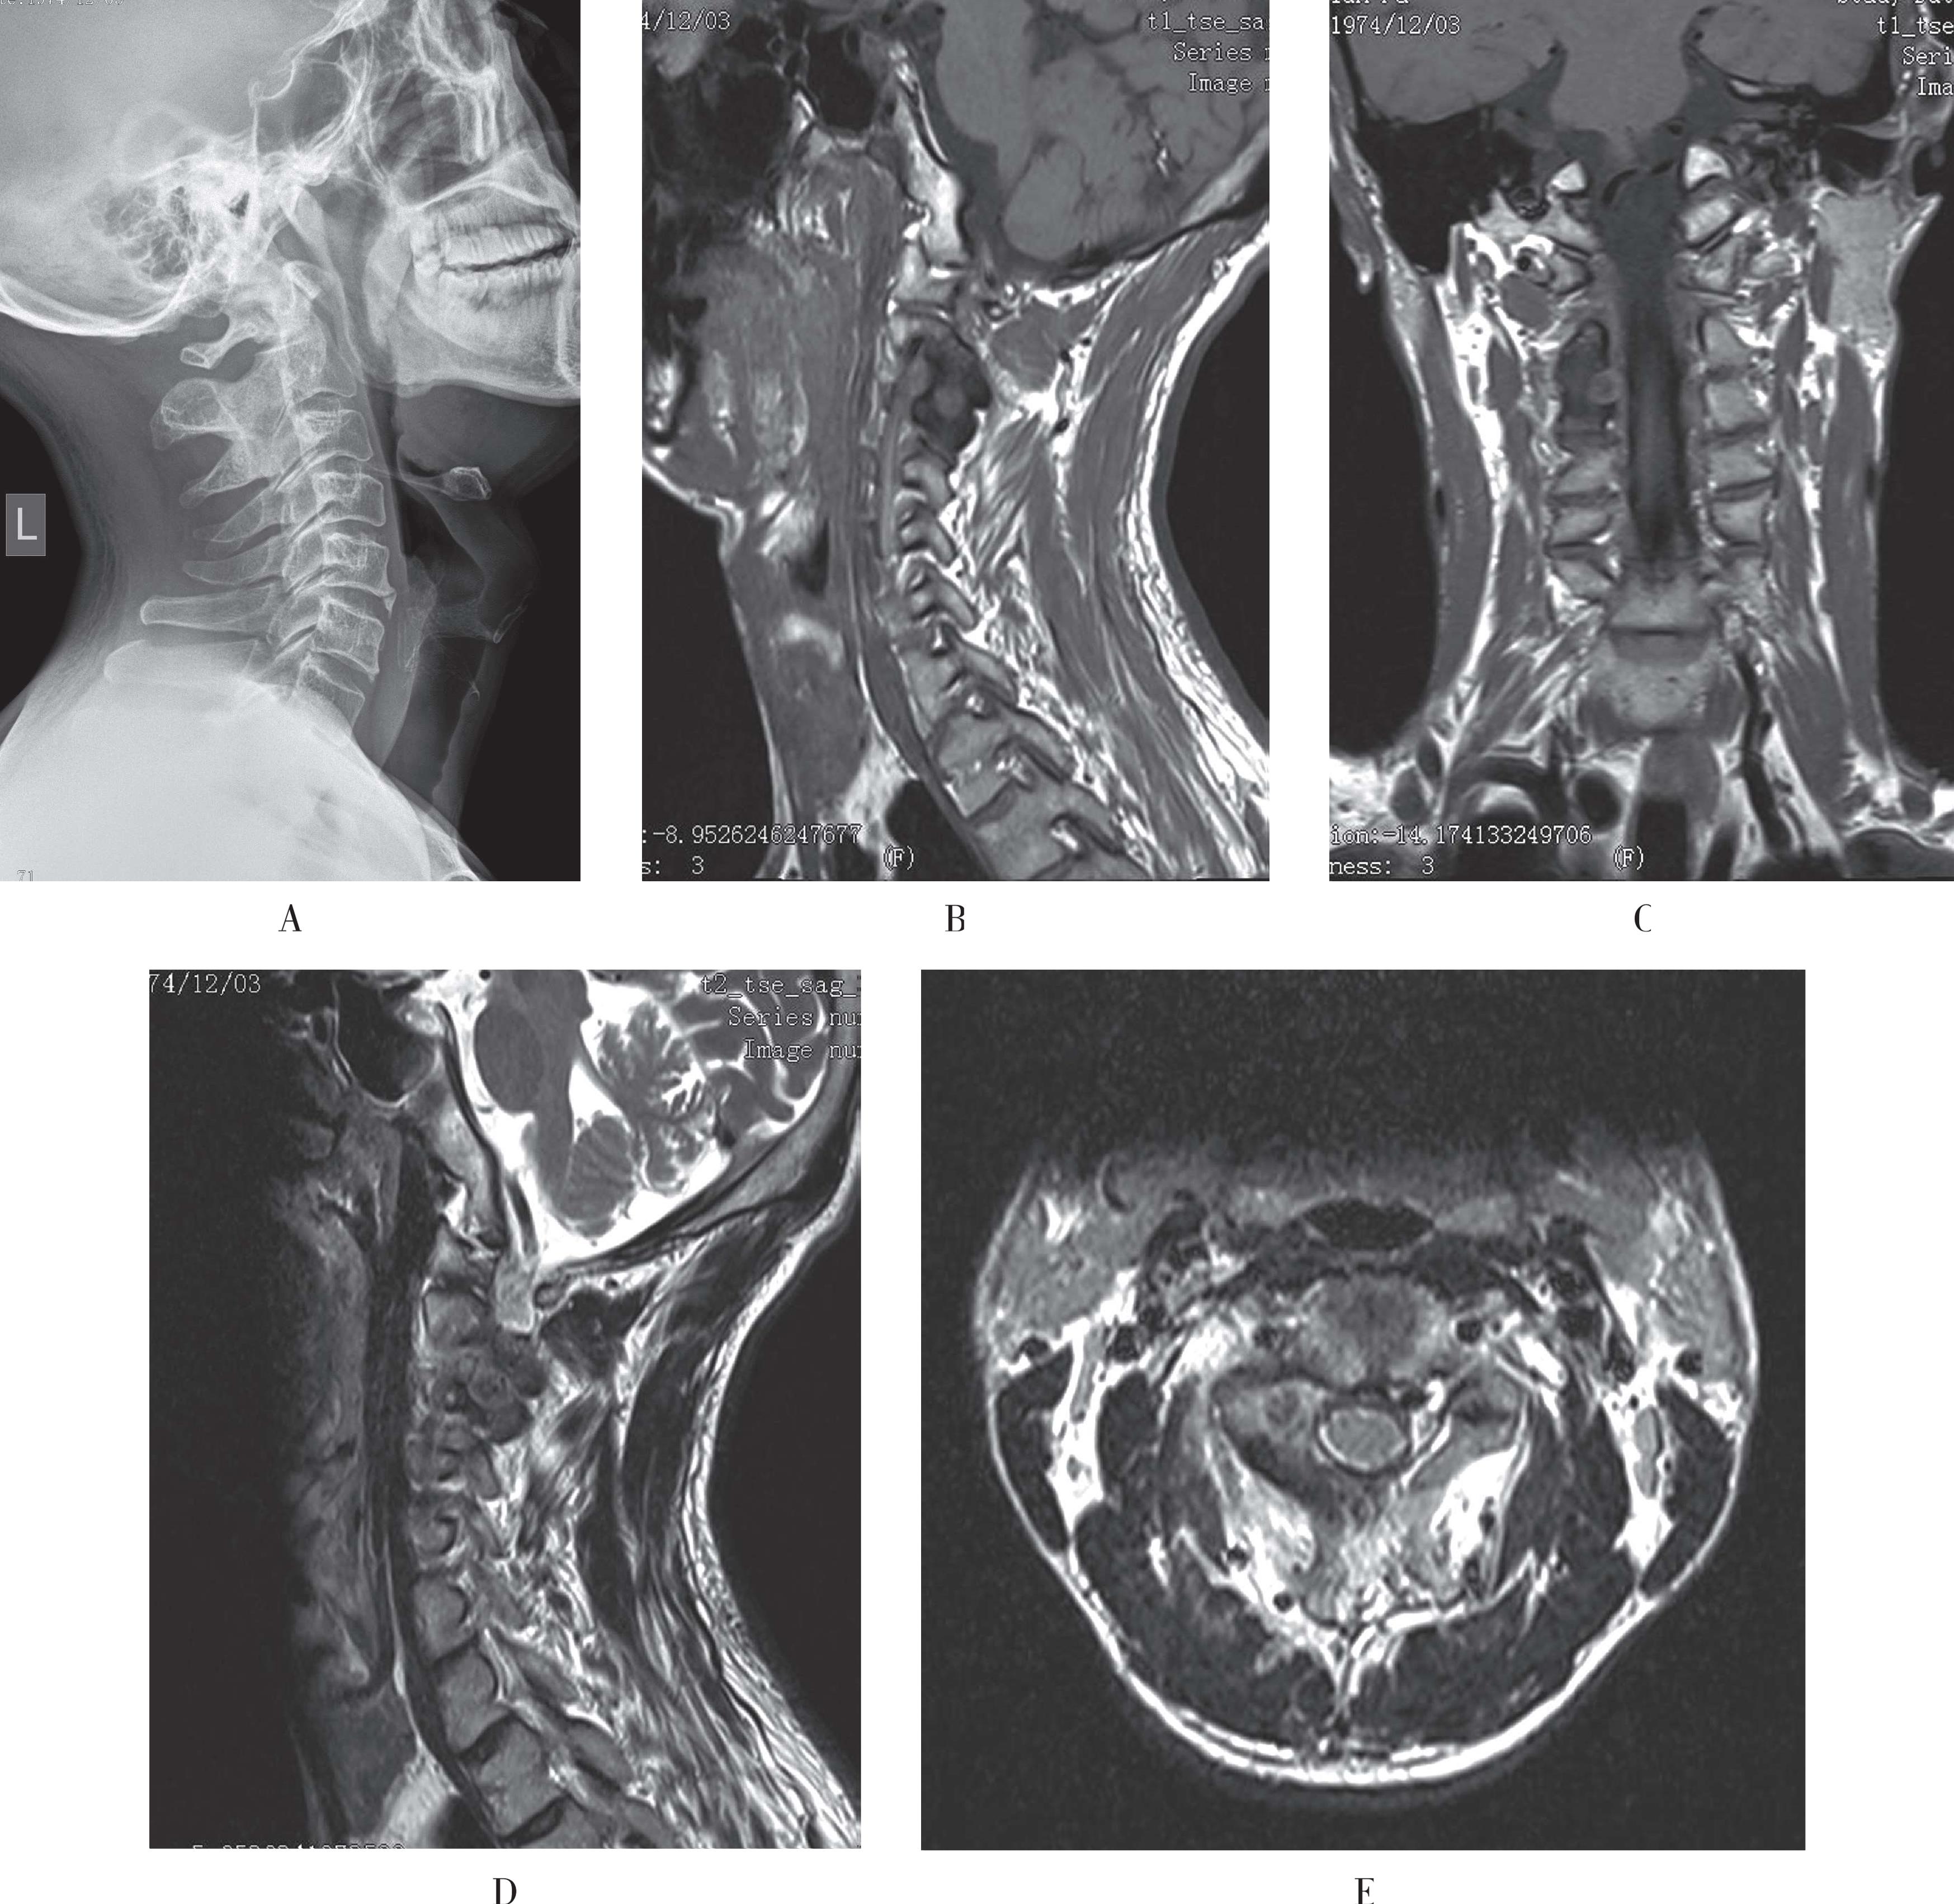

CT可明确显示病变,平扫显示骨髓腔内透亮区,正常骨结构消失,代之以粗大、稀疏的致密点,代表粗大稀疏的骨小梁,与X线所见的栅栏状骨小梁一致。与MRI相比,CT显示骨小梁更清晰,易与其他含脂肪较多的骨内占位性病变相鉴别(图3-50A)。

MRI特点较有特征性,在T1WI像和T2WI像均为高信号,压脂序列仍呈高信号,在高信号中尚见栅栏状低信号影,代表稀疏骨小梁,病灶边界清晰;增强扫描时有明显强化。随着MRI的广泛应用,脊柱血管瘤的检出率明显提高(图3-50B至3-50D)。

A.CT平扫示椎体中后部见片状透亮区,正常骨小梁结构消失,可见较粗大、稀疏的致密点;B.TIWI腰3椎体内见类圆形高信号,其内见条形低信号,界清;C. T2WI腰3椎体内病变以高信号为主;D. 压脂T2WI病变呈高信号,其内见条状低信号,代表粗大骨小梁

图3-50 脊柱血管瘤